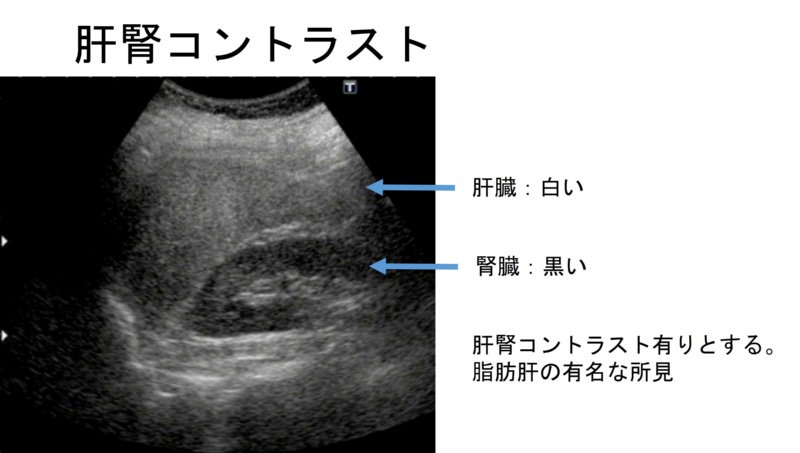

超音波検査で脂肪肝を,みて,見て,診よう 4。